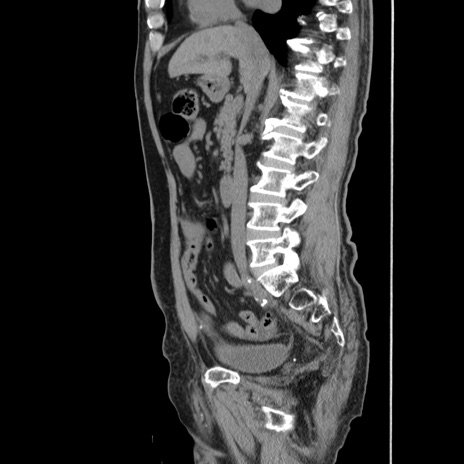

症例24(矢状断像)

【症例】80歳代男性

【主訴】左側腹部痛、嘔吐

【現病歴】本日早朝より左腹部に痛みあり。昼頃嘔吐認めたため、救急要請。

【既往歴】直腸癌(Mile手術)、胆摘

【身体所見】意識清明、BT 35.9℃、BP 221/93mmHg、SpO2 97%(RA) 、腹部:左ストーマ周囲に限局性の腹部膨隆あり。 膨隆部自発痛・圧痛あり・軟。

【データ】WBC 7700、CRP 0.09